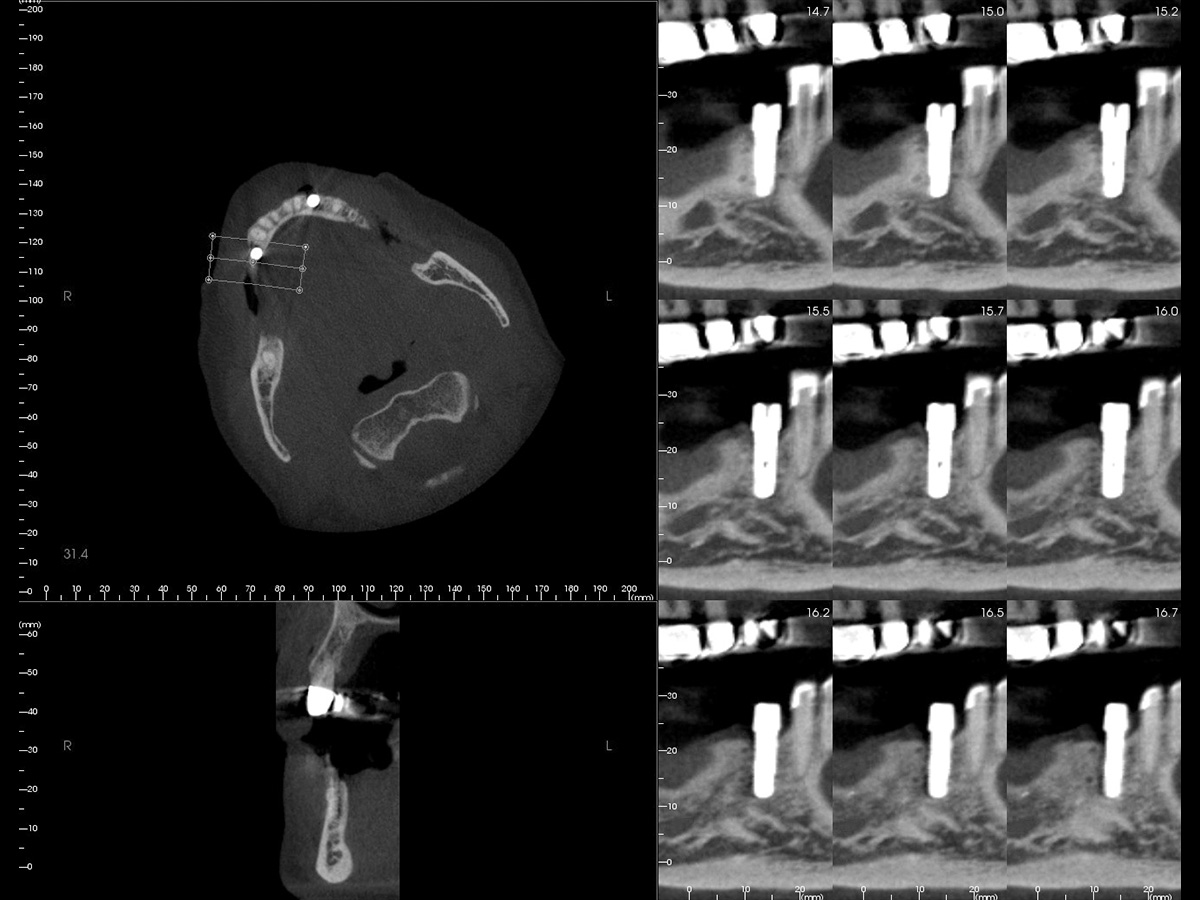

Abbildung 2

DVT mit Implantatplanung zeigt die atrophe Knochensituation mit geplantem Implantat.